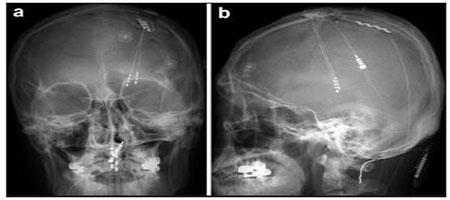

6. Long-term results of a simultaneous trial of deep brain and motor cortex stimulation in refractory neuropathic pain

Byung-chul Son, Jin-gyu Choi, Sang-woo Ha, Deog-ryeong Kim

临床转化神经科学    2017, 3 (1): 4-15.   DOI: 10.18679/CN11-6030/R.2017.002

摘要533)      PDF (2084KB)(519)

Objective: Although deep brain stimulation (DBS) and motor cortex stimulation (MCS) are effective in patients with refractory neuropathic pain, their application is still empirical; there is no consensus on which technique is better.

Methods: To enhance the success rate of trial stimulation of invasive neuromodulation techniques and identify approapriate stimulation targets in individual patients, we performed a simultaneous trial of thalamic ventralis caudalis (Vc) DBS and MCS in 11 patients with chronic neuropathic pain and assessed the results of the trial stimulation and long-term analgesia.

Results: Of the 11 patients implanted with both DBS and MCS electrodes, nine (81.8%) had successful trials. Seven of these nine patients (77.8%) responded to MCS, and two (18.2%) responded to Vc DBS. With long-term follow-up (56 ± 27.5 months), the mean numerical rating scale decreased significantly (P < 0.05). The degree of percentage pain relief in the chronic MCS (n = 7) and chronic DBS (n = 2) groups were 34.1% ± 18.2% and 37.5%, respectively, and there was no significant difference (P = 0.807). Five out of the seven MCS patients (71%) and both DBS patients had long-term success with the treatments, defined as >30% pain relief compared with baseline.

Conclusions: With simultaneous trial of DBS and MCS, we could enhance the success rate of invasive trials. Considering the initial success rate and the less invasive nature of epidural MCS over DBS, we suggest that MCS may be a better, initial means of treatment in chronic intractable neuropathic pain. Further investigations including other subcortical target-associated medial pain pathways are warranted.

图表 | 相关文章 | 多维度评价